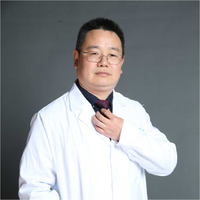

病灶1-4:两肺多处淡磨玻璃结节,密度低,散在,轮廓较清。

病灶5-6:左肺尖淡磨玻璃结节,轮廓较清。